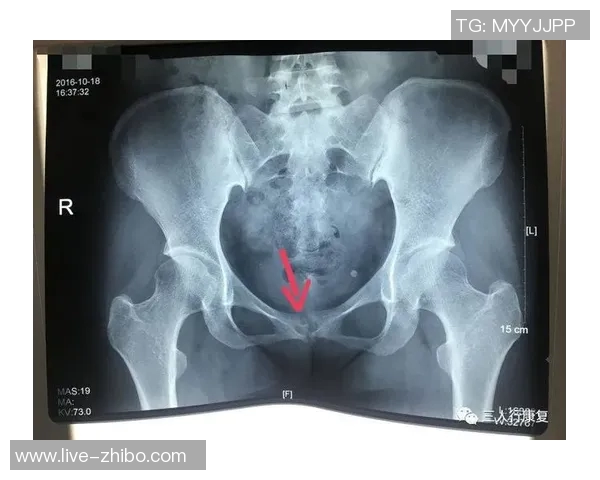

尼科·威廉姆斯是一名备受瞩目的年轻球员,他在比赛中表现出色,为球队贡献了许多关键进球。然而,在一次重要比赛中,他不幸遭遇了耻骨炎。这种疾病给他的训练和比赛造成了严重影响,让他不得不面对漫长而艰难的恢复过程。

初期,尼科并没有意识到自己的伤势有多严重。他依旧坚持参加训练,但随着时间推移,他逐渐感受到身体的不适。经过专业医生的检查后,他被确诊为耻骨炎,这让他深感沮丧,因为这意味着他需要停下脚步,进行长时间的康复治疗。